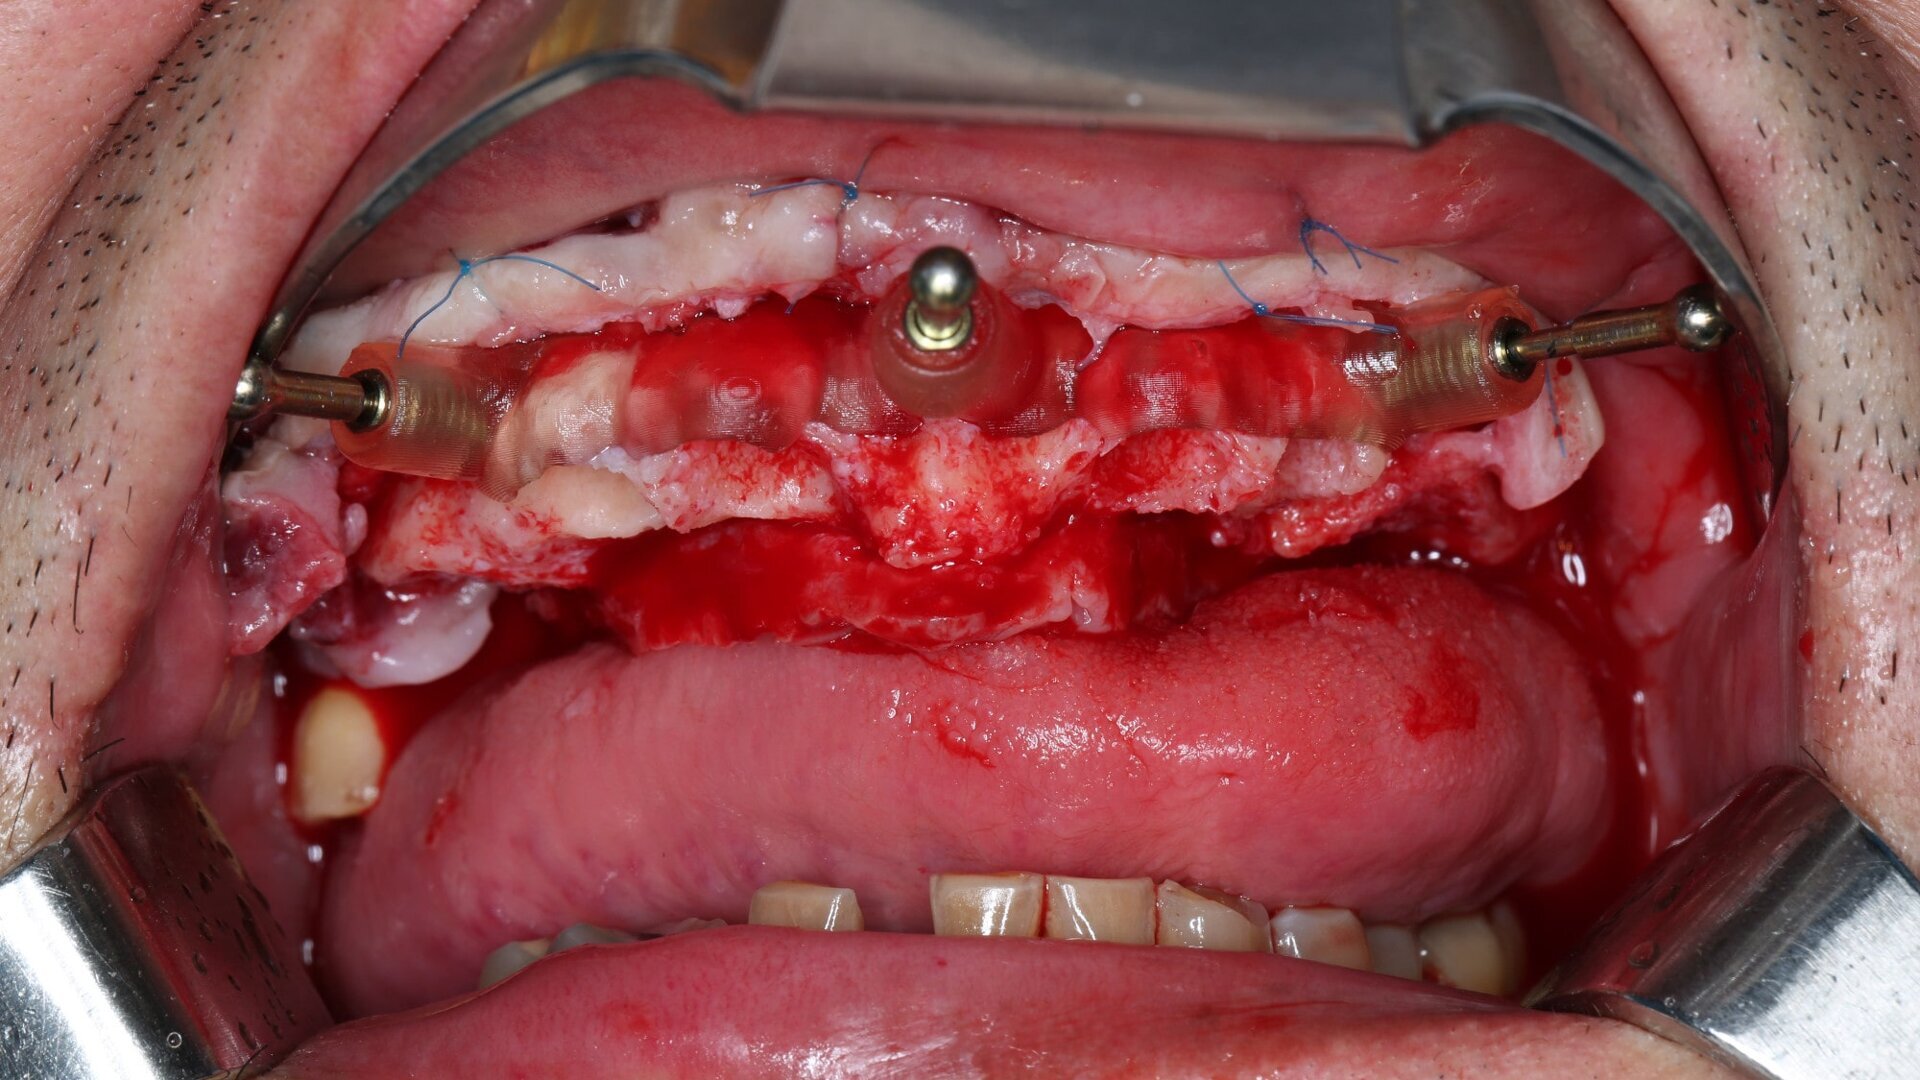

On the day of surgery, we prepared for the surgical protocol provided by the implant planning software, which guided us on the drilling sequence and the use of the appropriate instruments for the implant bed preparation (Figs. 30a & b). After the fixation pins had been allocated, teeth #17, 16, 15, 13, 12, 22, 23 and 24 were atraumatically extracted and alveolectomy was performed using a bone reduction guide (Figs. 31–36). Four implants (Straumann BLX; regular base; diameter: 4.5 mm; length: 12.0 mm) were placed, two straight implants in the anterior and two titled implants in the posterior. All the implants were stabilised to a torque of 50 Ncm (Figs. 37–43), and the SRAs were placed on top. The SRAs on the posterior implants had an angulation of 30° (diameter: 4.6 mm; gingival height: 3.5 mm) and on the anterior implants an angulation of 17° (diameter: 4.6 mm; gingival height: 3.5 mm; Figs. 44 & 45).

Teeth #17, 16, 15, 13, 12, 22, 23 and 24 were atraumatically extracted and alveolectomy was performed using a bone reduction guide. (Image: Dr Tran Thanh Phong, Vietnam)